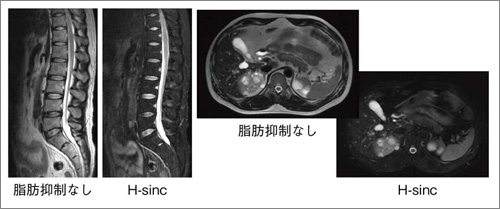

図6に,脊椎領域と体幹部のH-sincによる脂肪抑制画像を示す。H-sincでは,広範囲で高い脂肪抑制効果が得られている。図7は,膀胱腫瘍と右耳下腺腫瘍の脂肪抑制T2WIであるが,磁化率による不均一の影響を受けやすい頸部領域においても良好な脂肪抑制効果が得られている。

図6 H-sinc脂肪抑制の効果